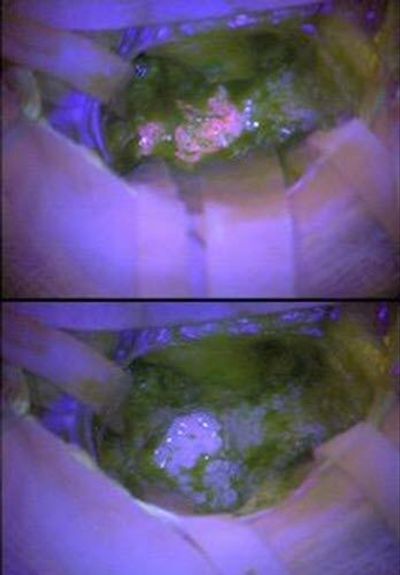

Fluorescence

Multisample Technique to Analyze Cell Adhesion